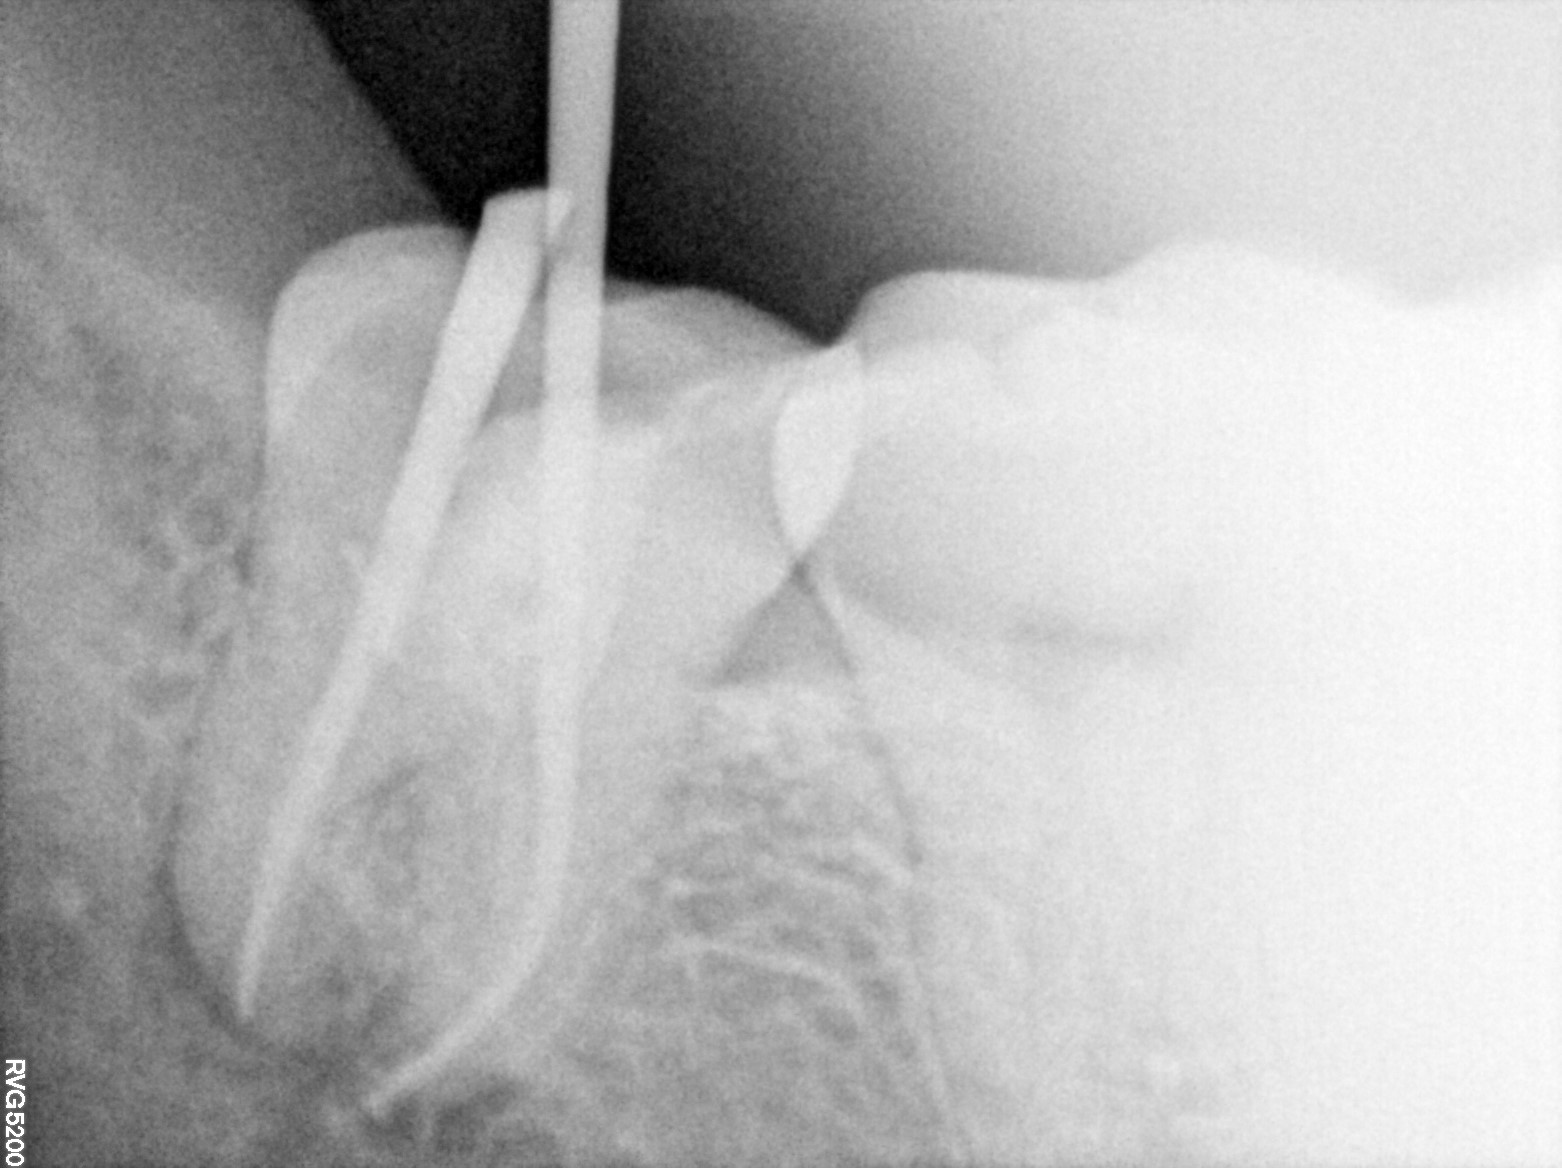

Dental Radiographs FHIR: DocumentReference · LOINC 24641-7

R74.jpg

24641-7